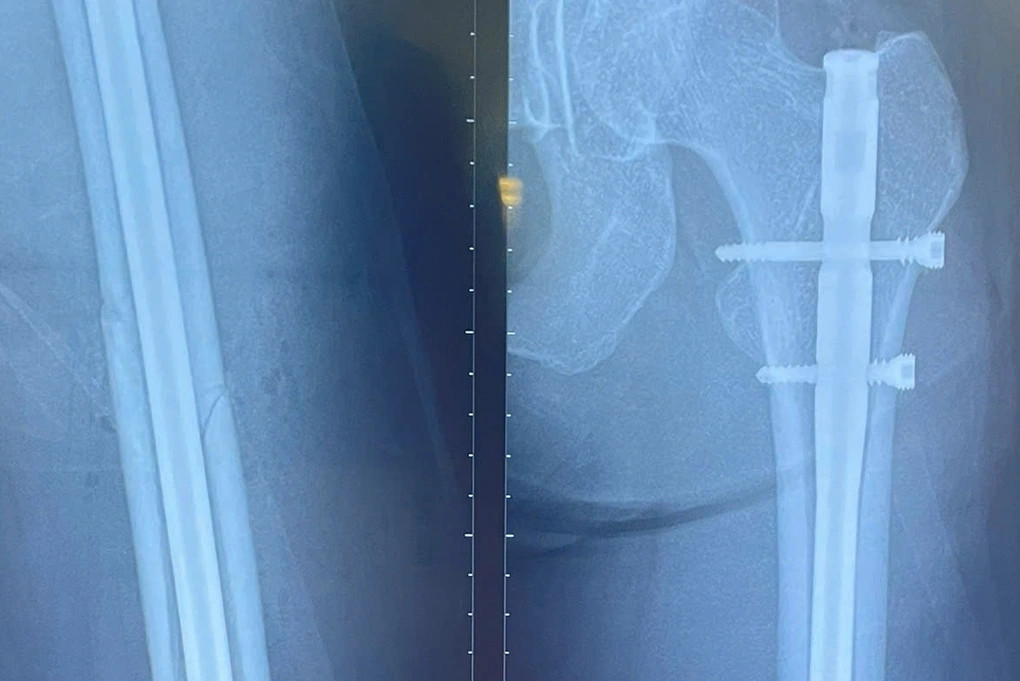

Nữ người mẫu 30 tuổi bất ngờ gặp tai nạn gãy xương đùi trên sân chơi pickleball tại TPHCM. Với chiều cao 1m78, đường gãy tét dọc xuống theo xương đùi trái nên ca mổ khó khăn hơn.

Bệnh nhân bị tai nạn tại một sân pickleball ở TPHCM và nhập viện để phẫu thuật cấp cứu trong tình trạng tổn thương đùi trái và kết quả chụp X-quang gãy 1/3 giữa thân xương đùi.

Theo bác sĩ Thắng, bệnh nhân cao đến 1m78, đường gãy xương tét dọc xuống theo xương đùi trái, nhiều đường chồng lên nhau nên ca mổ khó khăn hơn. Bác sĩ phải thực hiện đường mổ nhỏ, tránh ảnh hưởng thẩm mỹ cho người bệnh, nhưng phải đảm bảo đủ nắn chỉnh cố định để chống chân đi được sau một ngày phẫu thuật.

Hình ảnh gãy xương đùi của nữ người mẫu trên phim chụp. Ảnh: BVCC.

Trước ca phẫu thuật, các bác sĩ phải cân nhắc rất kỹ về vấn đề lựa chọn dụng cụ kết hợp xương và phải tư vấn, giải thích cho người bệnh về chế độ tập luyện, phục hồi. Ca mổ thực hiện lúc 14h ngày 4/4, bằng kỹ thuật đường mổ nhỏ đóng đinh với chốt 2 đầu xương đùi (đóng đinh chốt đùi). Hiện tại, sức khỏe bệnh nhân đang dần ổn định.